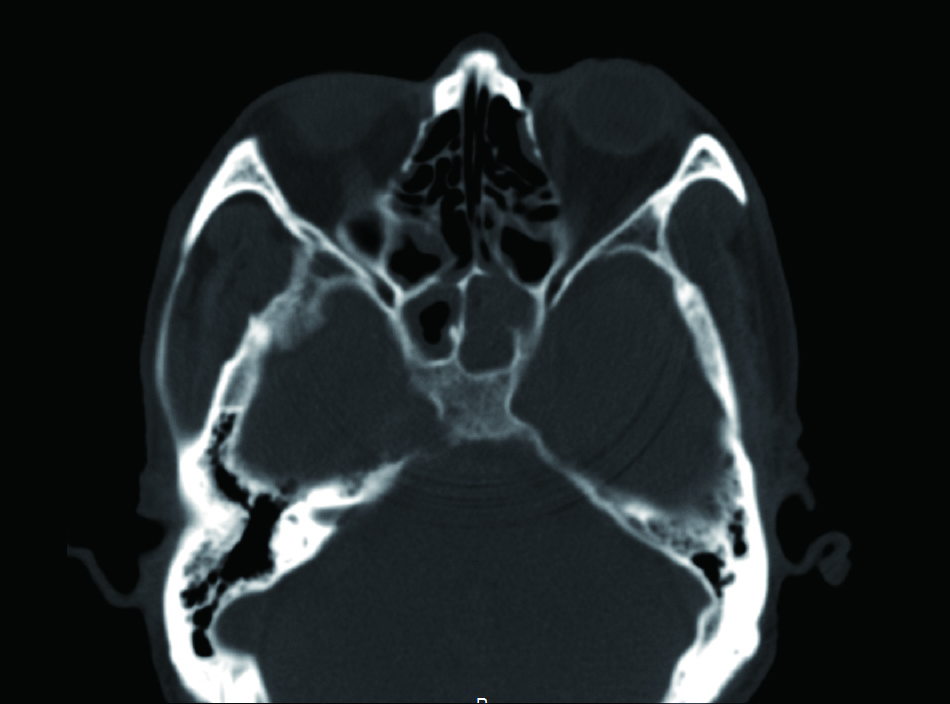

1 资料与方法病例1,患者男性,66岁,因头痛3周,复视1周入院。患者3周前起右侧太阳穴针刺样疼痛,影响睡眠。2周前出现咽痛鼻塞流涕及双耳听力下降,伴有右侧额部皮肤红疹,上述症状在当地医院治疗后减轻。1周前出现复视,当地医院治疗后症状无好转,诊断:颅内感染,多颅神经麻痹转来本院急诊。查体:神清,面部可见散在淡色丘疹,以右侧前额为主,右眼外展受限,面部痛触觉无殊,四肢肌力5级,病理反射阴性。脑脊液生化常规示:潘氏试验阳性,有核细胞970/μL;血沉28.00 mm/h,C反应蛋白14.1 mg/L。增强头颅MR提示两侧海绵窦增粗增宽,考虑炎症,并见双侧筛窦上颌窦蝶窦炎(图 1)。予头孢曲松钠2.0 g静脉注射抗感染治疗。治疗2周后头痛明显减轻,但复视症状无好转。复查血常规正常,C反应蛋白正常范围,血沉28.00 mm/h,脑脊液生化及常规正常范围。复查头颅增强MR提示病变范围较前无缩小。鼻窦CT提示双侧蝶窦炎症较前加重(图 2)。建议患者行鼻内镜下蝶窦手术。患者自觉症状减轻拒绝手术,要求出院。出院后在外院继续头孢曲松钠抗感染治疗。治疗10 d后因头痛复视症状无改善,并出现面颊部感觉减退再次入院。入院后查血常规,C反应蛋白正常,血沉28.00 mm/h,脑脊液潘氏试验阳性,细胞数量继续减少至60/μL。继续抗感染治疗。再次头颅MR及鼻窦CT复查提示海绵窦及蝶窦内病变较前范围增大(图 3),经多学科讨论,转本科行视频内镜下双侧蝶窦开放术。术后第三天鼻腔填塞物完全抽除后头痛症状明显缓解,术后6 d出院,头痛症状消失,复视仍存,出院后继续抗感染治疗,定期门诊复诊,术后6个月,复视症状消失。

| 图 3 蝶窦炎症较前加重 |